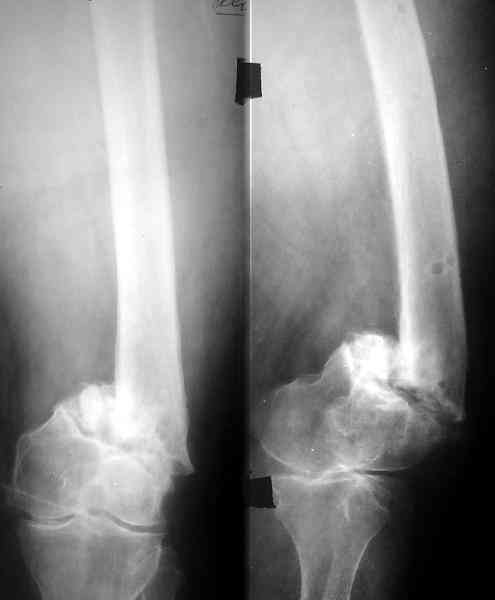

V> С моей точки зрения, адекватная фиксация любой металлоконструкции в

V> дистальном отломке бедренной кости невозможна. Поэтому вариантов

V> вмешательства два: либо ВКДО с фиксацией голени (что, учитывая

Аппарат для восстановления оси и длины тут действительно вполне уместен. И голень целесообазно врменно зафиксировать. А заштифтовать

можно и без голени, оставляя шансы на ту или другую мобилизацию коленного сустава.

Пример подобного ложного сустава в приложении.